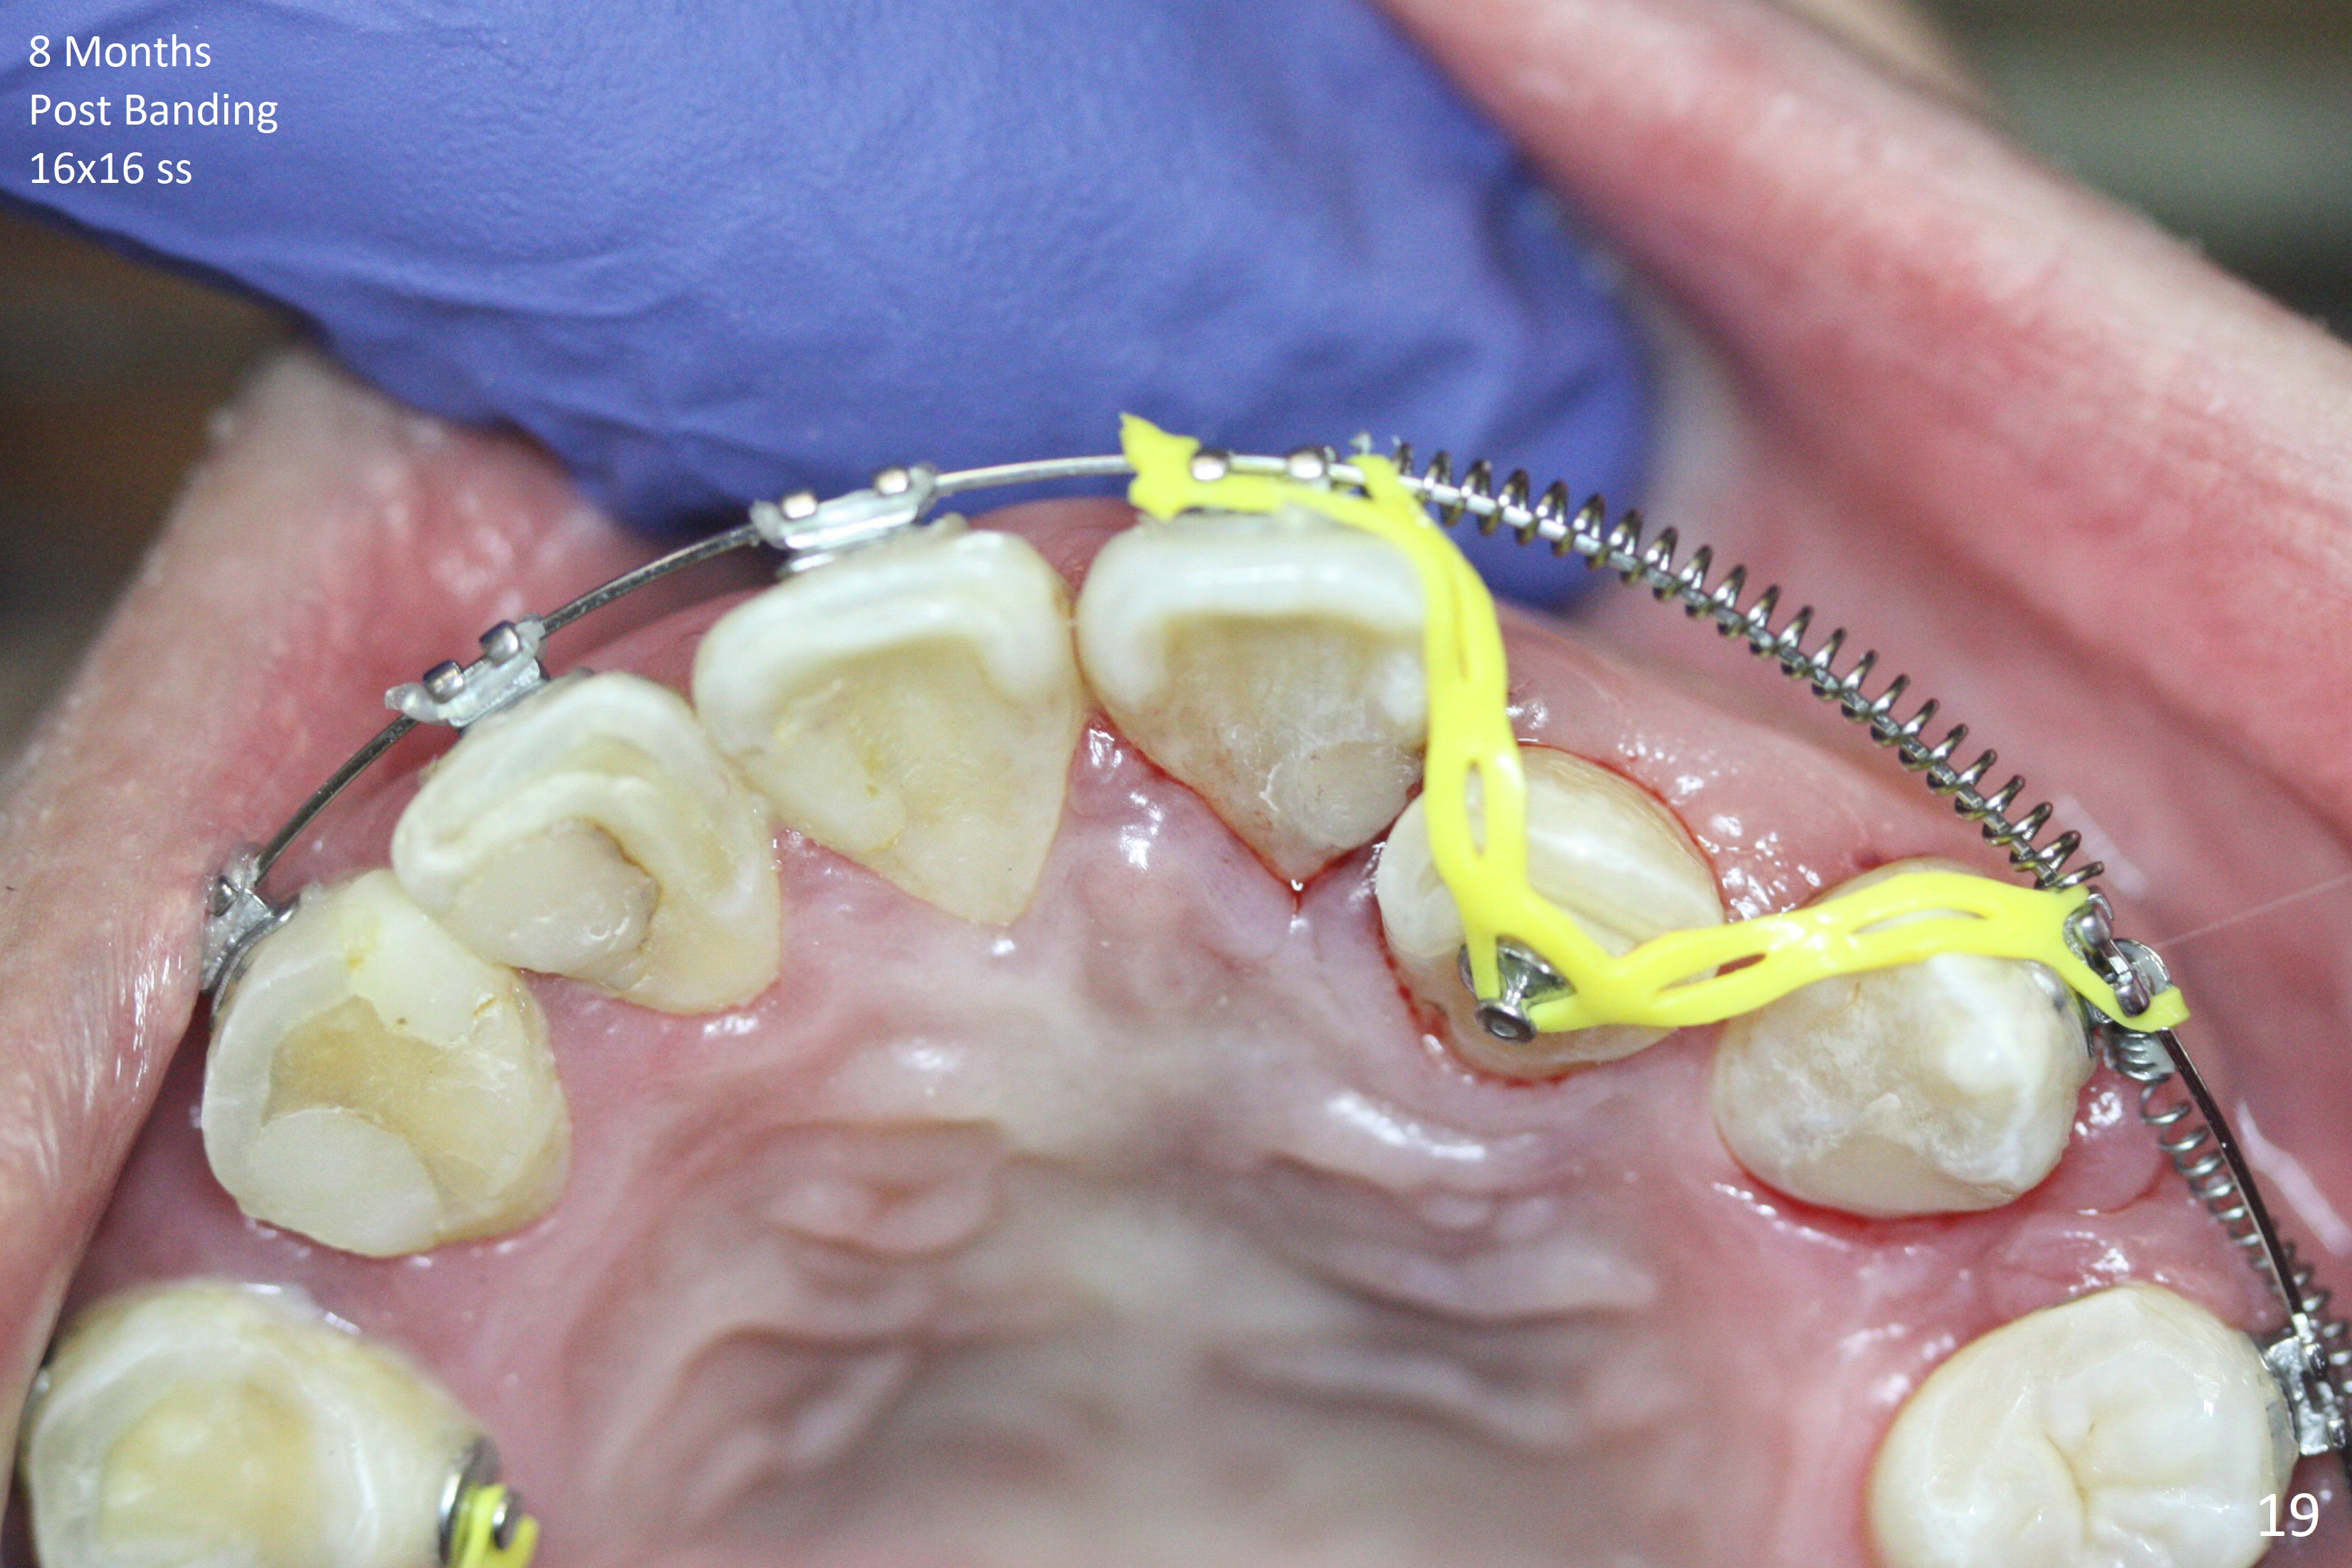

Severe crowding (Fig.1-7) appears to be alleviated especially 2 months after UR5 extraction. Diastemata seem to form mesial and distal to UR2 (Fig.8). Because of severe wear at UR3 (Fig.6), there is no bracket placement differential around it (Fig.8 (14 niti wire)). Lower bands and brackets are placed a week later (Fig.9-11). Because of tight space between LR4 and the opposing tooth (Fig.10), band adhesive is applied to L7 occlusal surface to open the bite (Fig.9). There is an abrupt kink of 12 niti wire between LL4 and 6 (Fig.11). The latter does not improve much in a month; the wires remain the same (Fig.12). For LL2, LR4 has been retracted for ~ 1 month (Fig.13). There is mild tension when 18 ss wire is inserted between LL4 and 6 five point five months post banding (Fig.14). UR4 has been distalized for a month using buccal power chains x3 resulting in rotation; to counter the rotation, a lingual button is placed with power chain x3 lingual and x2 buccal (Fig.15). With space gaining, it is time to finish definitive filling (Fig.16 *). Next visit check midlines, overjet, interdigitation, and molar classification. R4s distalize, but associate with rotation because of power chains buccal and lingual 8 months post banding (Fig.17,18). With the use of the same wires, power chains are applied lingual to continue distalization and rotation correction (Fig.20,21). Lingual buttons are placed at L2s buccalization (Fig.19) and mesialization (Fig.22,23). It appears that space should be created distal to LR3. That is that the lower anterior teeth should be shifted to the right, although it may be not appropriate for the midline.